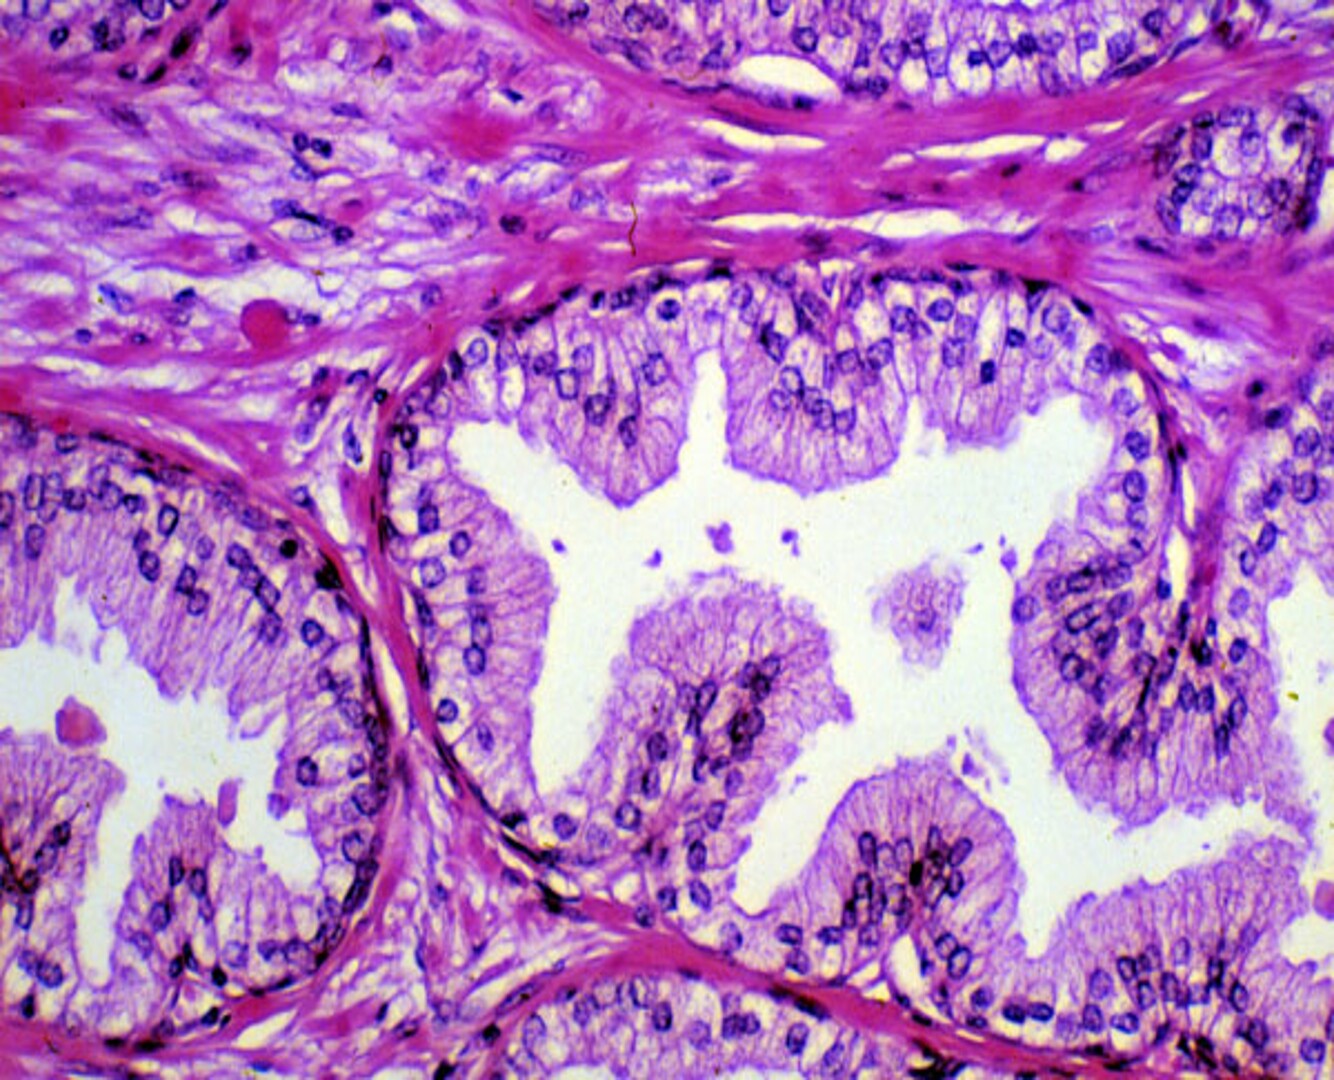

Benign Prostatic Hyperplasia

Glands are hyperplastic, papillary-like infoldings with myoepithelial cell layer (small nuclei near BM) What divides the glands from each other? The stroma (purple colour line) There is a double layer of columnar cells (there is normally a single layer) (the cells look normal, but there are just more in number)

Old man comes to you dribbling urine

BPH